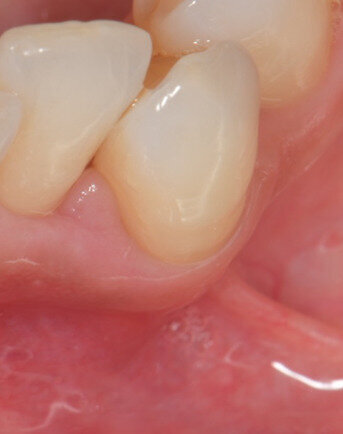

Fig. 7 - Visione frontale del difetto trattato a 30 giorni di follow-up. I parametri parodontali sono migliorati: PPD di 3 mm e CAL 4 mm. L’aspetto clinico dei tessuti è significativamente migliorato. L’edema della fase iniziale è rientrato e si nota una depressione al centro della papilla che evidenzia una fase avanzata della guarigione.